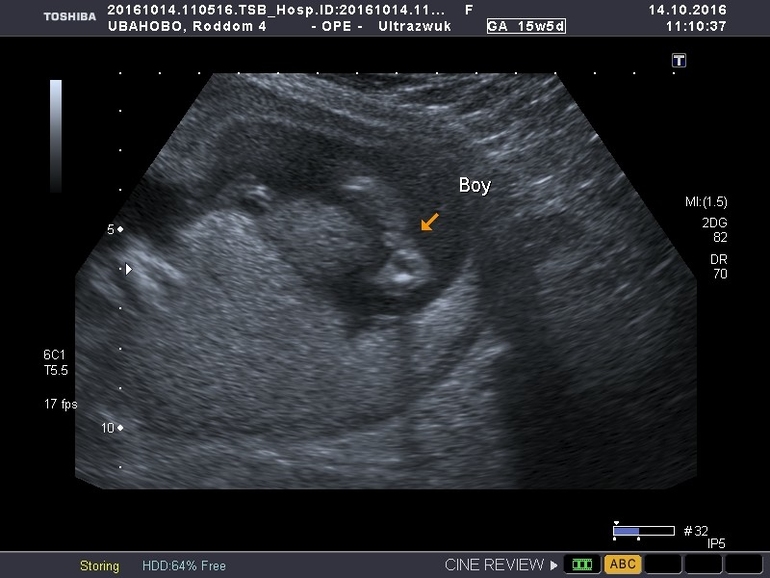

Здравствуйте.подскажите пожалуста может остались у кого фото с узи.срок 15.5 сказали мальчик.

Это мальчик да, у меня точно такое же узи с младшим сыном, а сейчас не дал малыш посмотреть..тайна в общем. Но знаете..в любом случае еще надежда есть..сходите на узи в 19-20 недель, там уж точно скажут.

во 2 Б на 15нед уверенно сказали мальчик,в 16 ещё один врач,в 20 нед узи подтвердило тоже